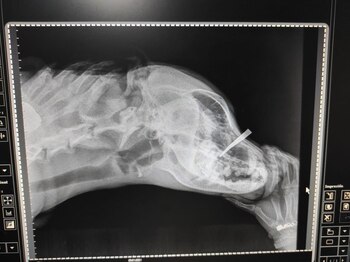

Según el ente acusador, el 9 de enero, a la altura del kilómetro 7, vía La Calera, Molina atacó, sin razón aparente y con unas tijeras, a Snoop, un perro de la zona, dejándole graves heridas y casi causándole la muerte.

Sin embargo, lo que se sabe es que el estado de salud de Snoop es complicado y que todavía se está recuperando de las graves heridas que le causó el agresor en su hocico y otras partes del cuerpo. Así lo han dejado ver en imágenes la Fundación Patitas Campesinas, los integrantes de la Junta Defensora de Animales de La Calera y Cundinamarca, quienes han apoyado en el proceso al animal y a la denunciante.

Destacó que, afortunadamente, el animal no murió a causa de las heridas, pero al ser heridas de gravedad su pronóstico se mantiene reservado.